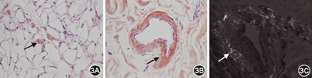

血常规:白细胞8.0×109/L,红细胞4.35×1012/L,血红蛋白125 g/L,血小板71×109/L,嗜中性粒细胞百分比80.4%;尿常规未见异常;肾功能:尿素氮11.9 mmol/L,肌酐107.8 μmol/L,尿酸471 μmol/L;N末端B型利钠肽原(NT-proBNP):2 101 ng/L(正常值<125 ng/L);D二聚体1 618.1 μg/L;甲状腺功能正常;肌钙蛋白I 0.15 μg/L(正常值<0.04 μg/L),肌酸激酶(CK)和肌酸激酶同工酶(CK-MB)在正常范围;红细胞沉降率7 mm/h;尿β2微球蛋白6.60 mg/L(正常值0~0.37 mg/L),尿微量白蛋白22.8 mg/L(正常值0~22.5 mg/L),血β2微球蛋白3.20 mg/L(正常值0.97~2.64 mg/L);血清蛋白电泳:清蛋白51.12%(正常值55.00%~68.00%),α1球蛋白8.16%(正常值1.00%~5.70%),α2球蛋白18.41%(正常值4.90%~8.80%),β球蛋白16.73%(正常值5.70%~10.40%),γ球蛋白5.58%(正常值9.80%~20.00%);血清免疫固定电泳:免疫球蛋白G升高,轻链κ升高;尿本周蛋白测定:轻链定量κ 0.040 g/L(正常值0~0.019 g/L),轻链定量λ<0.050 g/L(正常值0~0.050 g/L)。心电图示心房颤动,心室率78次/min,肢体导联低电压,右束支传导阻滞。肘静脉压力:右侧肘静脉压力为25 cmH2O(1 cmH2O=0.098 kPa),压肝后压力为35 cmH2O。发病2年以来,系列超声心动图示室壁逐渐增厚(图1),入院后超声心动图示左心房、右心房、右心室增大,左心室不大,左心房前后径36 mm,右心房内径45 mm×58 mm,右心室前后径31 mm,左心室舒张末期最大前后径37 mm,左心室壁弥漫性增厚,左心室后壁厚度16 mm,室间隔厚度19 mm,右心室壁厚度7 mm,室壁回声呈毛玻璃样,左心室壁弥漫性运动减弱,二尖瓣关闭不全(轻度),三尖瓣关闭不全(重度),主动脉瓣关闭不全(轻微),左心室收缩和舒张功能减退,左心室射血分数28%,少量心包积液。心脏磁共振及钆延迟增强扫描示:右心房和右心室增大,左右心室壁增厚;黑血序列显示左右室心肌内可见散在斑点状高信号影;延迟增强扫描可见右心房、室间隔、左右心室心肌呈弥漫性强化(图2)。腹部皮肤及皮下脂肪组织活检(图3):皮下纤维细胞增生,玻璃样变;纤维、血管壁及脂肪组织可见刚果红染色阳性的特殊物质沉积,不除外淀粉样变性。骨髓活检:刚果红染色阴性。骨髓细胞学检查:骨髓增生明显活跃,浆细胞比例偏高(占7.5%),排除多发性骨髓瘤。本病例确诊为免疫球蛋白轻链型心脏淀粉样变性,住院期间给予利尿和改善心功能治疗后,症状有所缓解,NT-proBNP较前无明显降低。

心脏淀粉样变性的特点:(1)临床表现[1]:早期为心脏舒张功能障碍,以后发展至限制型心肌病,有右心衰竭的症状和体征,如颈静脉压增高、右心室奔马律、肝脏肿大和外周水肿,部分患者发展为难治性充血性心力衰竭。(2)心电图特点[1]:表现为标准肢体导联低电压和胸前导联R波递增不良(类似于恢复期前间壁心肌梗死波形),常伴有心房颤动和传导阻滞。(3)超声心动图特点[1]:表现为心室壁和室间隔明显对称性肥厚,左心室心腔正常或缩小,左心室舒张功能减退;同时,心肌特征性回声增强,呈颗粒状闪烁样表现;此外,还可有心房扩大、瓣膜增厚或反流、心包积液、晚期伴有心室充盈压增高的限制性表现。(4)心脏磁共振特点[2]:弥漫性和(或)透壁性钆延迟强化。(5)核素:心肌99Tcm焦磷酸盐闪烁照相表现为同位素浓集的阳性影像(因99Tcm焦磷酸盐可以结合到与淀粉样纤维相关的钙分子上)。(6)组织活检[1]:心内膜活检是心脏淀粉样变性最直接的确诊方法,但取材困难。鉴于淀粉样变性为全身性疾病,多累及全身各个部位,故临床上可以采用心肌外活检代替心肌活检。如果在心脏以外活检发现淀粉样物质沉积,结合超声心动图和心电图特征性改变,也可确诊,无需再做心内膜活检。皮下脂肪垫活检结合骨髓刚果红染色对淀粉样变性患者的组织学诊断率达90%。刚果红染色在偏光下产生苹果绿样折射,是淀粉样变性最特异的染色。另外,也可在电子显微镜下观察淀粉样物质沉积。